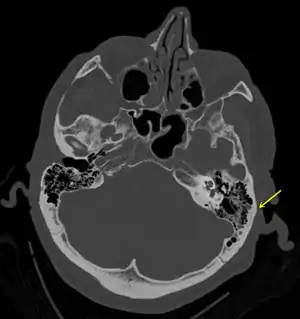

Temporal bone fractures

Acute injury to the internal carotid artery (carotid dissection, occlusion, pseudoaneurysm formation) may be asymptomatic or result in life-threatening bleeding. They are almost exclusively observed when the carotid canal is fractured, although only a minority of carotid canal fractures result in vascular injury. Involvement of the petrous segment of the carotid canal is associated with a relatively high incidence of carotid injury.[9]